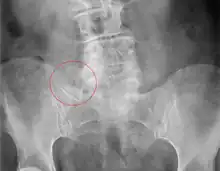

X-ray of Bertolotti's syndrome (in this case, right transverse mega-apophysis of L5 with pseudoarticulation with the sacral ala). Woman 67 years old. |